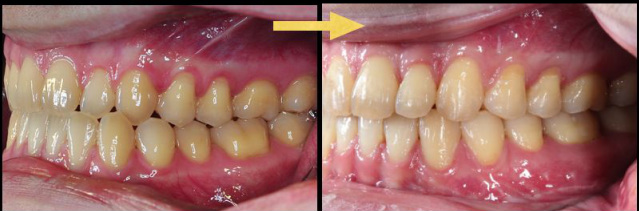

歐先生有一點厚道的狀況,下排牙齒較為突出,嘴巴也無法緊閉。

經過正顎手術之後,原先突出的下顎,回到正常的位置了。

矯正前,嘴巴無法緊閉,厚道

矯正後,下顎回到的完美位置